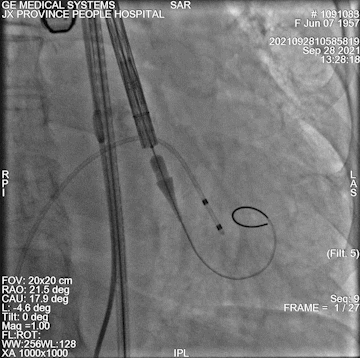

球囊扩张

球扩后左冠开口到左冠瓣距离

术中情况:术中超声及造影评估,左冠灌注未受影响,瓣膜释放后无明显下滑,洪浪院长术中使用VitaFlow Liberty™进行操作,并精准释放,超声及时辅助评估,VitaFlow二代可回收功能给术者增加信心,可以更放心、大胆的挑战高风险病例。